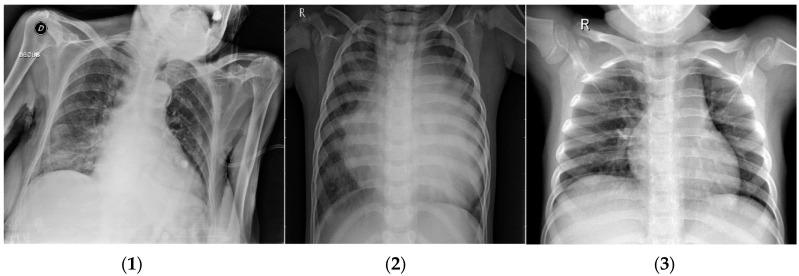

Medicine is one of the fields where the advancement of computer science is making significant progress. Some diseases require an immediate diagnosis in order to improve patient outcomes. The usage of computers in medicine improves precision and accelerates data processing and diagnosis. In order to categorize biological images, hybrid machine learning, a combination of various deep learning approaches, was utilized, and a meta-heuristic algorithm was provided in this research. In addition, two different medical datasets were introduced, one covering the magnetic resonance imaging (MRI) of brain tumors and the other dealing with chest X-rays (CXRs) of COVID-19. These datasets were introduced to the combination network that contained deep learning techniques, which were based on a convolutional neural network (CNN) or autoencoder, to extract features and combine them with the next step of the meta-heuristic algorithm in order to select optimal features using the particle swarm optimization (PSO) algorithm. This combination sought to reduce the dimensionality of the datasets while maintaining the original performance of the data. This is considered an innovative method and ensures highly accurate classification results across various medical datasets. Several classifiers were employed to predict the diseases. The COVID-19 dataset found that the highest accuracy was 99.76% using the combination of CNN-PSO-SVM. In comparison, the brain tumor dataset obtained 99.51% accuracy, the highest accuracy derived using the combination method of autoencoder-PSO-KNN.

医学是计算机科学取得重大进展的领域之一。一些疾病需要立即诊断以改善患者预后。计算机在医学中的应用提高了精度并加速了数据处理和诊断。为了对生物图像进行分类,本研究采用了混合机器学习,即各种深度学习方法的组合,并提供了一种元启发式算法。此外,还引入了两个不同的医学数据集,一个涵盖脑肿瘤的磁共振成像(MRI),另一个涉及新冠肺炎的胸部X光(CXR)。这些数据集被引入到包含深度学习技术的组合网络中,这些技术基于卷积神经网络(CNN)或自动编码器,以提取特征并将其与元启发式算法的下一步相结合,以便使用粒子群优化(PSO)算法选择最优特征。这种组合旨在降低数据集的维度,同时保持数据的原始性能。这被认为是一种创新方法,并确保在各种医学数据集中获得高度准确的分类结果。使用了几种分类器来预测疾病。在新冠肺炎数据集中,使用CNN-PSO-SVM组合的最高准确率为99.76%。相比之下,脑肿瘤数据集的准确率为99.51%,这是使用自动编码器-PSO-KNN组合方法得出的最高准确率。